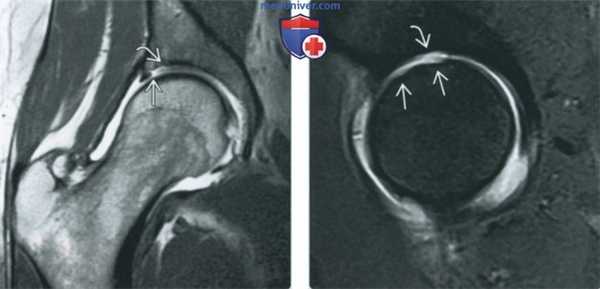

(Слева) МР-артрография в режиме PD FS, сагиттальный срез: визуализируется зернистое скопление жидкости в суставной тубе, распространяющееся от ее суставной поверхности к капсуле. Суставная туба в характеризуется неровным контуром. Выявленные изменения соответствуют разрыву.

(Справа) МР-артрография в режиме PD FS, аксиальный срез, этот же пациент: выявляется крупная паралабральная киста, узкая шейка которой сзади ведет к области разрыва суставной губы. Наличие паралабральной кисты, которая в данном случае визуализируется только с использованием чувствительных к жидкости последовательностей, является важным признаком разрыва. (Слева) МР-артрография в режиме PD FS, сагиттальный срез: визуализируется разрыв суставной губы, распространяющийся от ее суставной поверхности к капсуле. Сквозное распространение дефекта на всю толщину тубы до поверхности суставной капсулы позволяет отличить небольшой разрыв от сублабраль-ной борозды.

(Справа) Артроскопия, этот же пациент: зондом разведены фрагменты суставной губы, подвергшейся сквозному разрыву. Fla снимке головка бедренной кости расположена слева. (Слева) МР-артрография в режиме Т1ВИ FS, коронарный срез: между костью и суставной губой выявляется ровный контур щели. Такая картина соответствует варианту нормы.

(Справа) МР-артрография в режиме PD FS, сагиттальный срез, этот же пациент: визуализируется ровный контур сублабральной щели. При артроскопии было подтверждено отсутствие разрыва. Дифференциальная диагностика между разрывом и щелью может быть затруднена, однако в пользу щели свидетельствуют ровные контуры. Кроме того, щель никогда не проходит на всю толщину суставной губы.